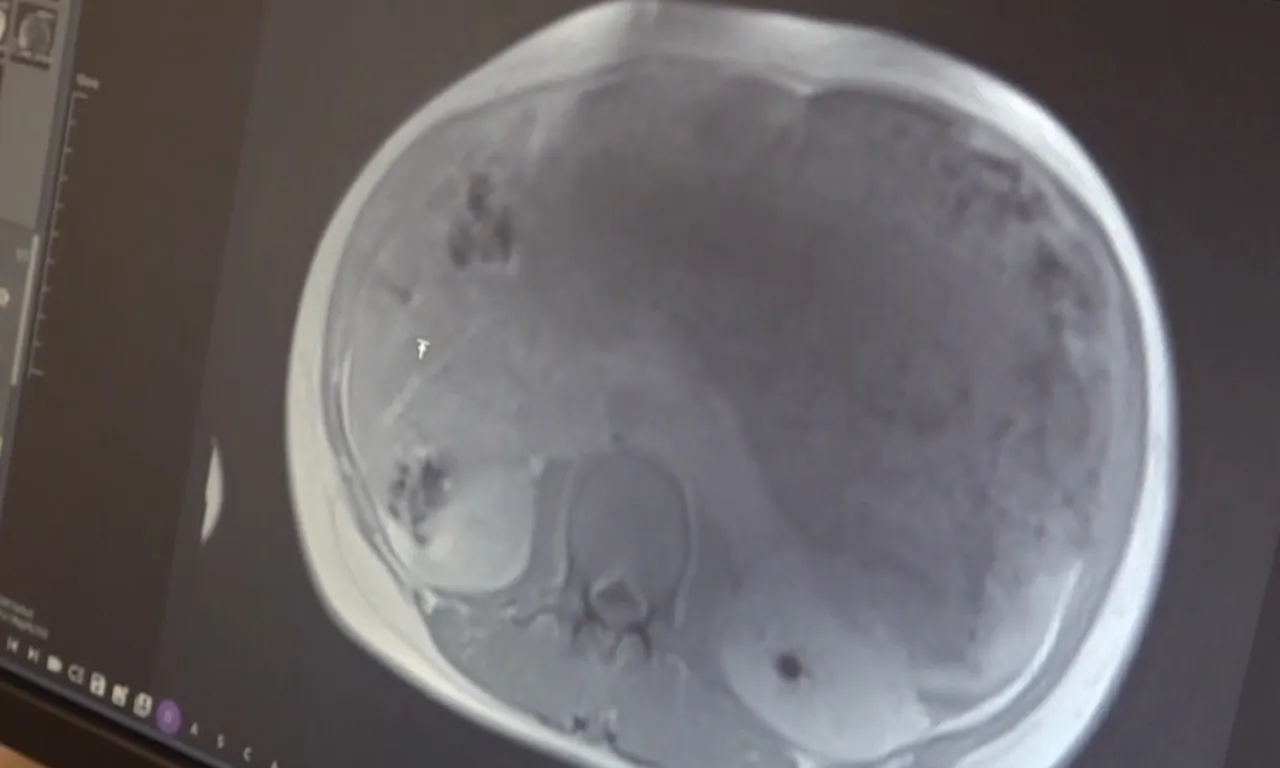

Prof. Dr. Ersin Gündoğan ise mideden kaynaklı bir kitleyle karşılaştıklarını belirterek, mide ve karaciğerin bir kısmı ile bağırsak damarlarını besleyen yağlı dokunun da bir kısmıyla kitlenin çıkarıldığını anlattı.

Kitlenin büyüklüğüne dikkati çeken Gündoğan, "Karın içi organlarından daha fazla yer kaplayan bir kitlesi vardı. Daha önce tedavi başlanmış, tedaviye rağmen büyümüş. Yaklaşık 45 santimlik bir kitleden bahsediyoruz. Bağırsak hareketlerini ve solunum hareketlerini engelleyecek kadar bası yapan bir kitle vardı. Karnı o kadar gergindi ki doğuma yaklaşmış gebe gibiydi. Bu kadar büyük kitlenin etrafa yayılmama olasılığı yok” diye konuştu.